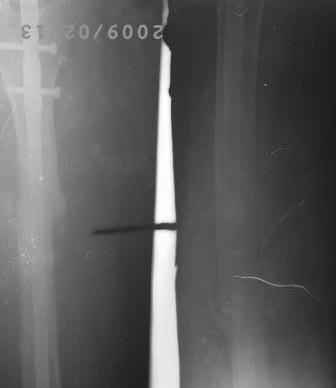

12.02.09г б-ная оперирована: з/остеоклазия (без особого труда- видимо тугой ложный сустав) коррекция деформации, удаление штифта из надвертельной обл, рассверливание канала гибкими развертками, реостеосинтез блокируюшим гвоздем Д-11мм.

Но я впервые почувствовал такую сильно ОСТЕОПОРОТИЧНУЮ кость, что блокируюшие винты проваливаются внутрь кости, что винты можно ввести без сверления кости, и что винты провинчиваются холостую, т.е. не стабильно.

P.S. Снимки не качественные, извиняюсь! последний снимок ЭРГА, два снимка объединил.

Я заранее приношу свои извинения, но по демонстрации видно, что сама методика БИОС использована с нарушениями. Да я с Вами согласен и сам часто встречался подобными случаями, когда из-за отсутствия функции конечности (опорной и двигательной) поврежденный сегмент теряеть минеральную плотность, тем самым развивается остеопороз. Однако Вам надо было заранее учитывать эти моменты и дистальные винты надо было установить четко бикортикально, в Вашем случае верхний дистальный винт короткий, нижний дистальный винт вне отверстия, в таком расположении он никак не может быть в блокирующем отверстии. Ранняя опорная нагрузка зависит от стабильности синтеза, веса пациента, но в любом случае дозированная нагрузка (собственный вес конечности) нужна, иначе срастить ложный сустав и ликвидровать остеопороз невозможно (кость должна выполнять свою функцию). С уважением Ерсин Жунусов.

Действительно из-за сильного остеопороза операция для меня была

очень трудной! тем более мы БИОС начали недавно это 6-по счету.

Гвозди мы закупали из предприятия ЦИТО, и если Вы заметили у них нижнее дистальное отверстие продолговато-овальное, а не круглое, поэтому оно позволяет ввести винт и под углом, конечно это тоже ошибка, ну два последних винта было введено из одного маленького разреза - поэтому так получилось!

Больная активизирована, начала ходить с костылями, с дозированной нагрузкой.